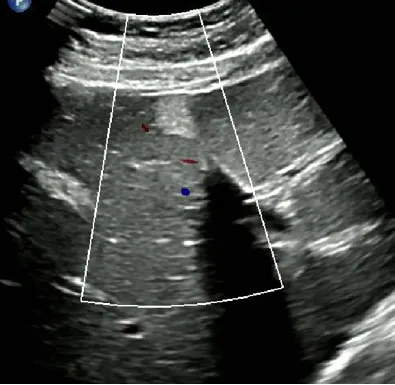

肝血管瘤

● 单发或多发,圆形或椭圆形、边界清晰、回声多样。

● 后方回声可不同程度增强。

● 探头加压可变形、对血管及邻近组织无浸润。

● CDFI:常无明显血流信号,或少量低速血流信号。